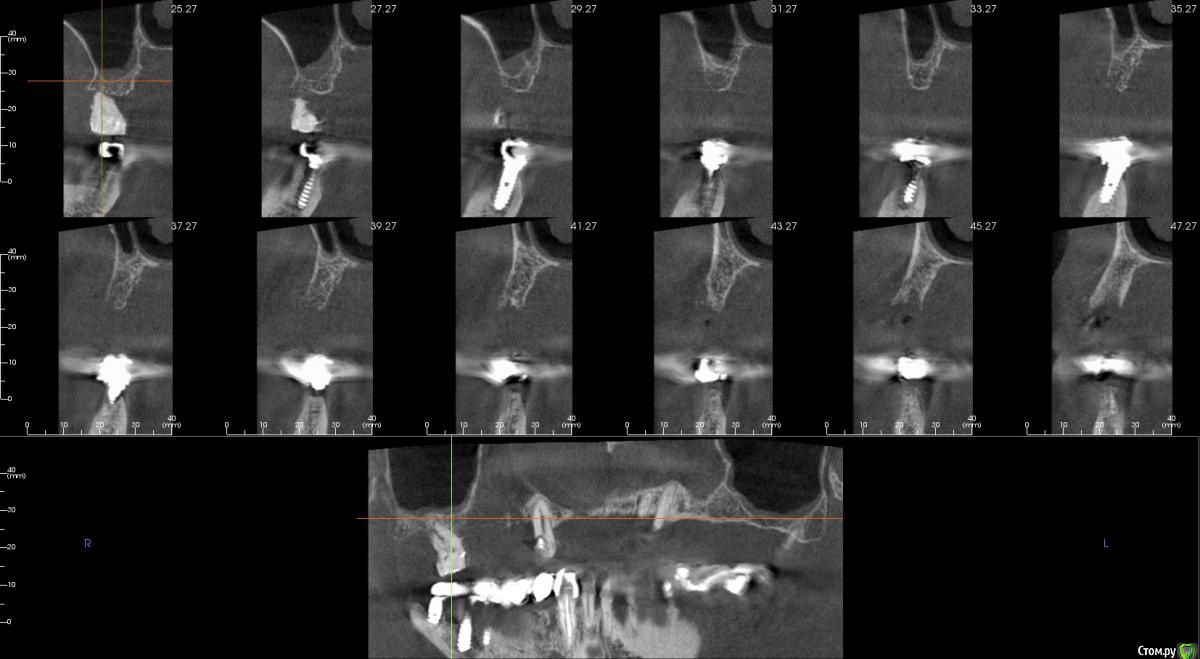

kamranchick Опубликовано 20 сентября, 2016 Поделиться Опубликовано 20 сентября, 2016 Интересует сторона 2. там хочу сделать соссидж, через несколько месяцев сделать закрытый синус и установить 2 винта в области 14 и 16, как вы думаете?и можно ли сделать конструкцию не брав во внимание фронтальный отдел? пациент финансово не тянет фронт Ссылка на комментарий

колесников Опубликовано 20 сентября, 2016 Поделиться Опубликовано 20 сентября, 2016 думаю не получится, так как придется аугментировать и фронтальный отдел и боковой отдел чтобы по хорошему сделать все на 4, тем более я работаю на Осстем, а у нас мультиков в системе нетНе нужно там ничего аугментировать. Меняете корни на импланты. В обл премоляров так же есть объём по снимку. Иначе череда костных и мягкотканных пластик с неясным прогнозом. Пациент точно не потянет. У остема платформа 4.0 совместима с астровской 4.5-5.0. Можно у астры взять запчасти. Ссылка на комментарий

kamranchick Опубликовано 22 февраля, 2017 Автор Поделиться Опубликовано 22 февраля, 2017 Интересно что в итоге получилось, какой метод выбрали?во фронте блоки в области 2 сегмента сосидж Ссылка на комментарий